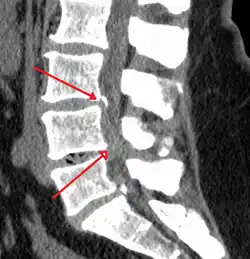

The diagnosis of spinal stenosis involves a complete evaluation of the spine. The process usually begins with a medical history and physical examination. X-ray and MRI scans are typically used to determine the extent and location of the nerve compression.

MRI

MRI has become the most frequently used study to diagnose spinal stenosis. The MRI uses electromagnetic signals to produce images of the spine. MRIs are helpful because they show more structures, including nerves, muscles, and ligaments than seen on X-rays or CT scans. MRIs are helpful in showing exactly what is causing spinal nerve compression.